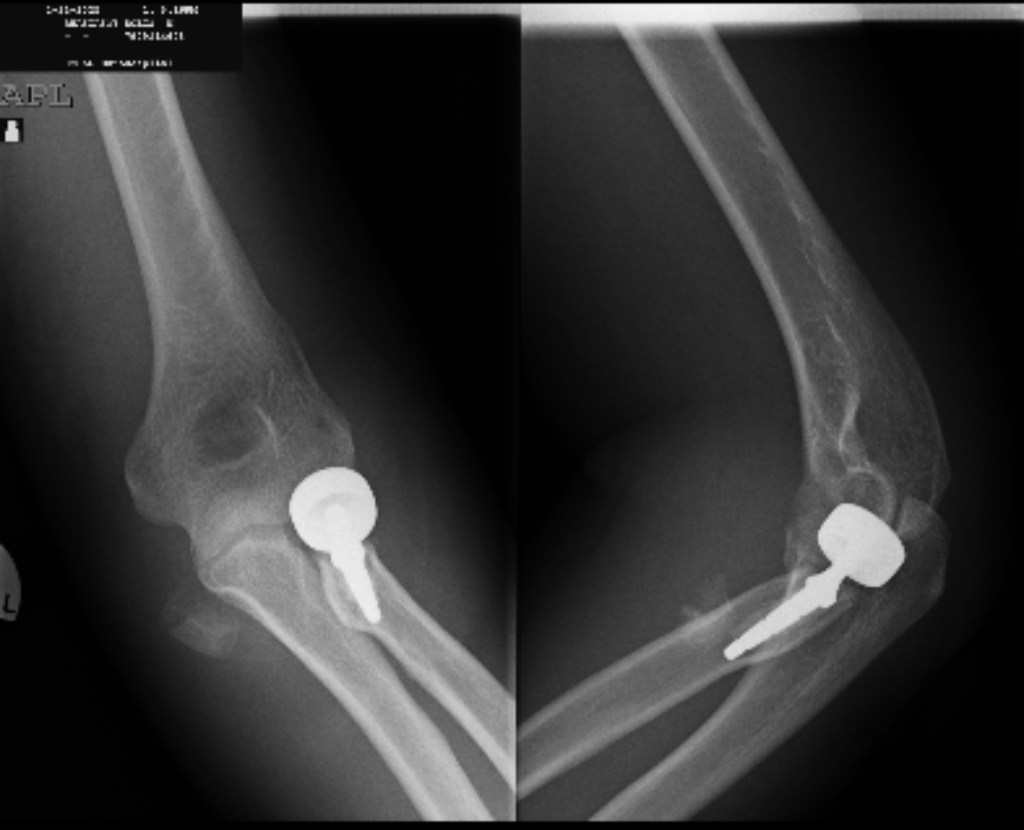

За първи път в Пловдив се извърши операция по частична артропластика на лакътна става след фрактура и луксация на ставата. Операцията бе извършена в отделението „Ортопедия и травматология“ на УМБАЛ „Еврохоспитал Пловдив“.

Частичната артропластика представлява изкуствена протеза, заменяща нефункционалната и проблемна част от лакътната става. Уникалността на операцията се състои в това, че се заменя проксималния край на лакътната кост, отговарящ за фините движения на предмишницата.

Пациентът е мъж, на 50 години, адвокат по професия. Три дни след операцията започва физиотерапия и активно раздвижване на лакътната става. Пълното възстановяване без болка се очаква след 45 дни.